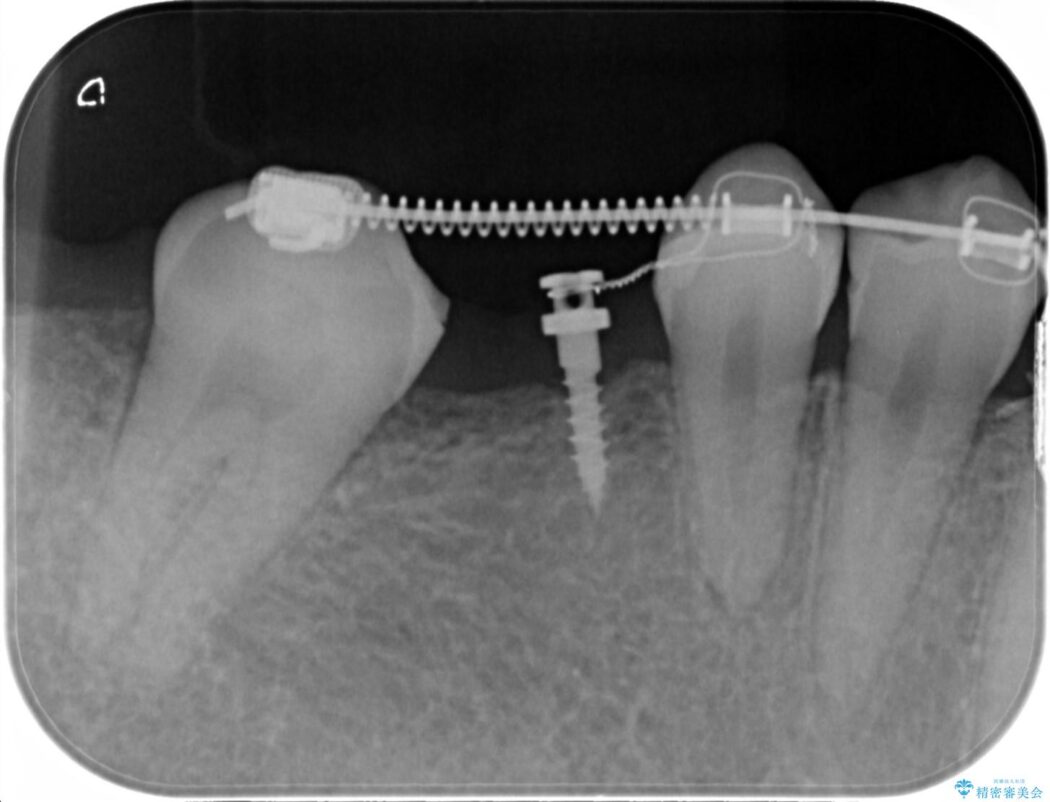

診査した結果、欠損した状態で長期間放置していたことが原因で最高峰の奥歯が欠けた部分に向かって傾斜してしまっていました。

この状態のままブリッジ治療へと進んでしまうと神経が露出する可能性が否定できないため、まずワイヤー装置による部分矯正で歯軸を通常位置へ戻してから補綴治療を行うこととしました。

本症例では、健康な歯を可及的に守るため神経の処置を避けた上で部分矯正を併用して行うことにより、安全に補綴治療(ブリッジ)ができました。